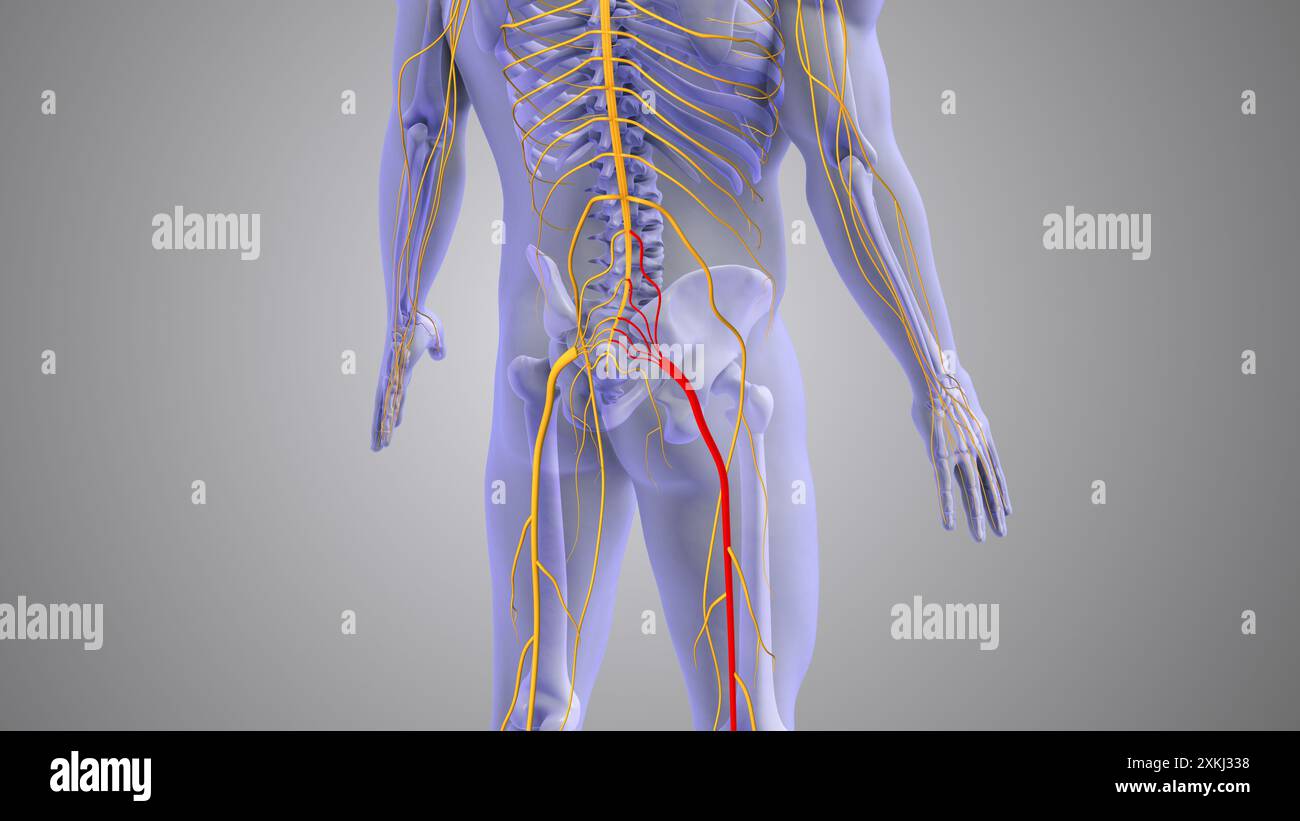

Medizinisches Konzept für Ischiasnervenbeschwerden Stockfotohttps://www.alamy.de/image-license-details/?v=1https://www.alamy.de/medizinisches-konzept-fur-ischiasnervenbeschwerden-image614438920.html

Medizinisches Konzept für Ischiasnervenbeschwerden Stockfotohttps://www.alamy.de/image-license-details/?v=1https://www.alamy.de/medizinisches-konzept-fur-ischiasnervenbeschwerden-image614438920.htmlRF2XKJ334–Medizinisches Konzept für Ischiasnervenbeschwerden

Medikamentöse Vorstellung von Ischiasnervenschmerzen Stockfotohttps://www.alamy.de/image-license-details/?v=1https://www.alamy.de/medikamentose-vorstellung-von-ischiasnervenschmerzen-image614438924.html

Medikamentöse Vorstellung von Ischiasnervenschmerzen Stockfotohttps://www.alamy.de/image-license-details/?v=1https://www.alamy.de/medikamentose-vorstellung-von-ischiasnervenschmerzen-image614438924.htmlRF2XKJ338–Medikamentöse Vorstellung von Ischiasnervenschmerzen